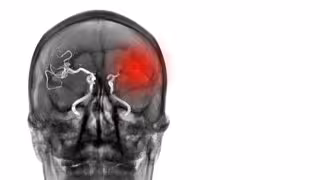

Desarrollan una herramienta para predecir el riesgo de rotura del aneurisma

Archivo - Aneurisma

Archivo - Aneurisma - SITTITHAT TANGWITTHAYAPHUM/ISTOCK - Archivo